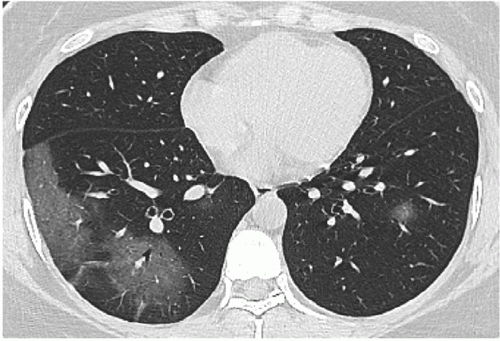

Something clicked for me reading Ricky’s Substack article “30 Clues That Let Us Know COVID Was A Planned Operation | Part VIII: EVALI” and I can’t stop thinking about it. He points out that the lung injury labeled as “COVID lung” looked almost identical to what doctors were already seeing in heavy vape users for years. Ground glass imaging. Scarred bronchioles. Oxygen exchange that never quite recovers. The clinical picture of bronchiolitis obliterans, more commonly called popcorn lung. The common factor is not some mythical viral enemy. The common factor is heat… plus nanoparticles.

Radiologists call the result “COVID lung” or “popcorn lung”. The mechanism has been staring us in the face for years. It’s. So. Simple. Call it what you want. Popcorn lung. Hair product lung. COVID lung. Nanoparticle lung. Not a virus making my long not work lung.